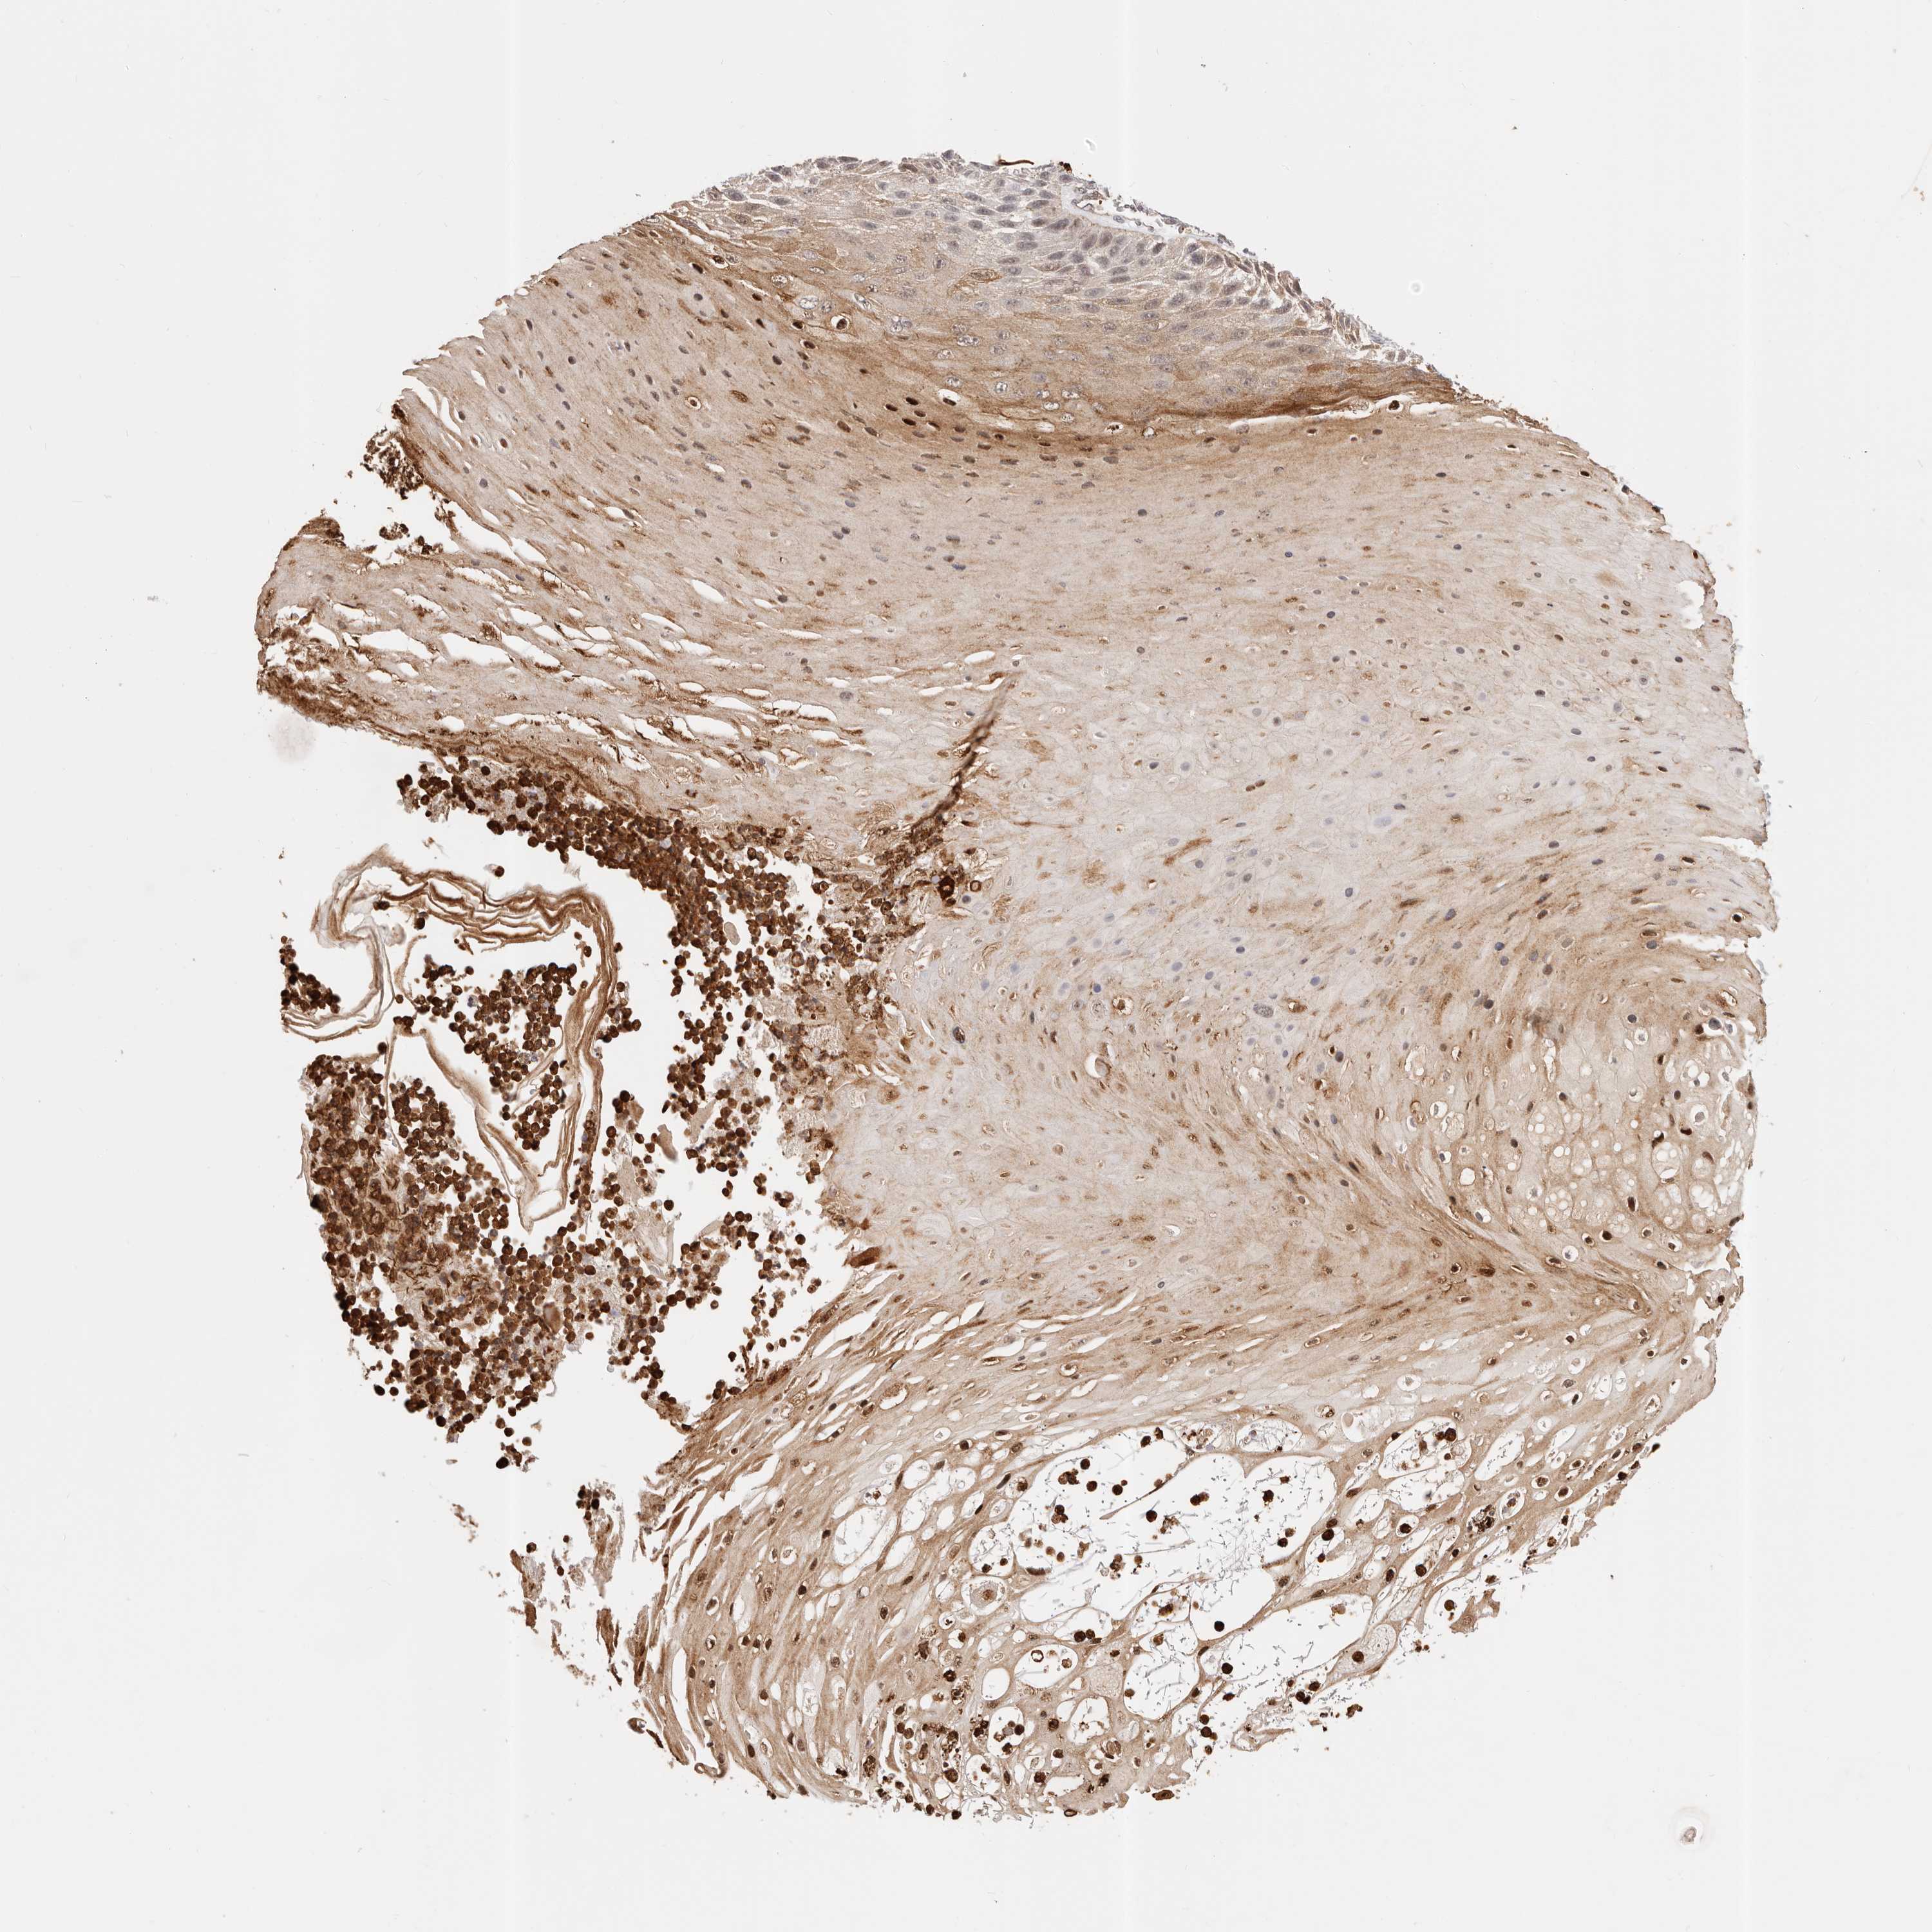

SKIN CANCER - Protein expressioni

A mouse-over function shows sample information and annotation data. Click on an image to view it in a full screen mode. Samples can be filtered based on level of antibody staining by selecting one or several of the following categories: high, medium, low and not detected. The assay and annotation is described here.

Antibody stainingi

Antibody staining in the annotated cell types in the current human tissue is reported as not detected, low, medium, or high, based on conventional immunohistochemistry profiling in selected tissues. This score is based on the combination of the staining intensity and fraction of stained cells.

Each image is clickable and will lead to virtual microscopy that enables deeper exploration of all samples and also displays staining intensity scores, fraction scores and subcellular localization as well as patient and tissue information for each sample.

Basal cell carcinoma

Squamous cell carcinoma, NOS

Squamous cell carcinoma, metastatic, NOS

Adnexal tumor, benign